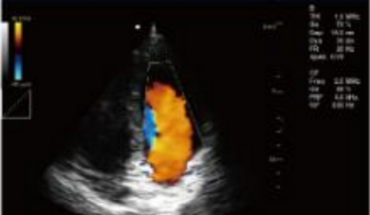

- B+CF (Images doubles)

- B+CF/DPDI+PW (Triplex)